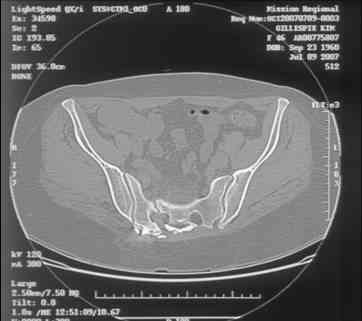

Here is a magnified view. Sorry about the quality but the CT was scanned into our system.

I can't see the axial CT images well enough to detail the potential sacral issues....can you magnify them?

Thank you...it might help to remove the disengaged and other iliosacral screws then insert longer lag screws into the upper sacral segment and if anatomically feasible into the second sacral segment as well.